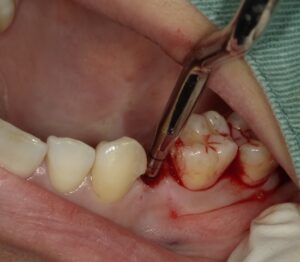

画像はオステオトームテクニックといいドリルを用いて

埋入する予定のインプラントの長さの1mm短くドリルした

穴にオステオトームという器具で叩いて約1mmの骨を骨折させて

上顎洞粘膜を破らずに持ち上げる手術になります。

この場合は、外側内側の骨は十分ありましたのでフラップレスと

いい歯肉を切開しない方法でソケットリフトができました。

そのため縫合も必要ありません。